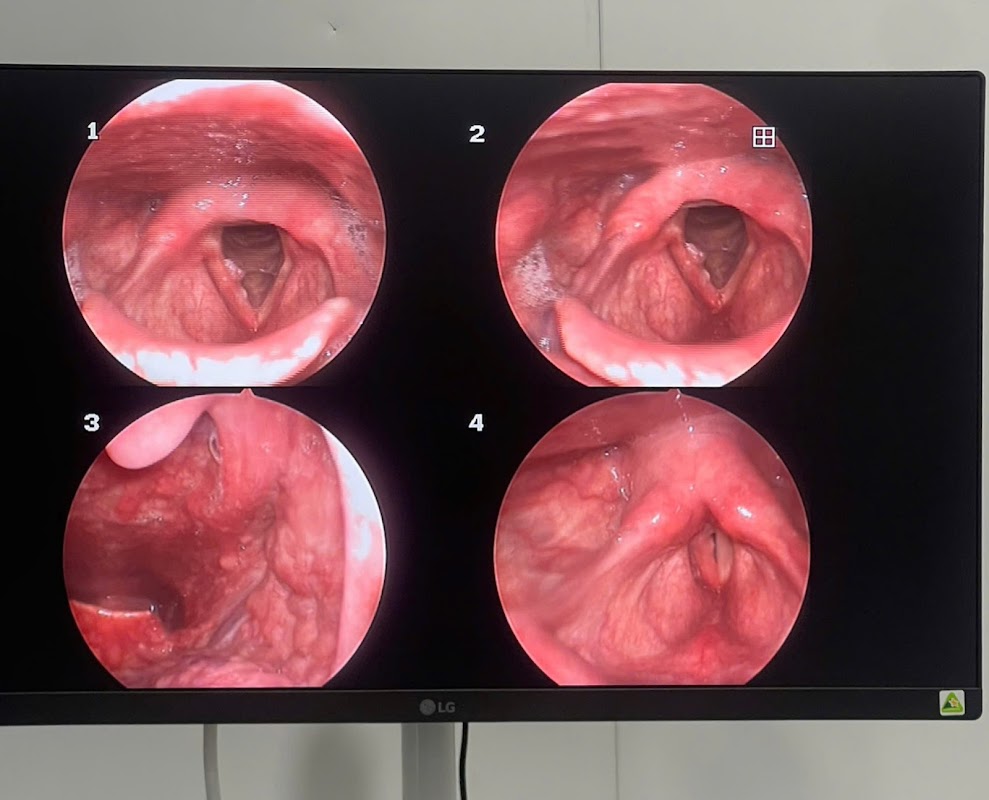

- **Không gian và phòng ốc:** Phòng khám được bố trí gọn gàng, có khu vực chờ sạch sẽ với vài bộ ghế nhựa khá ổn. Phòng khám mình vào khám được trang bị đầy đủ máy móc cơ bản phục vụ việc khám tai mũi họng như máy soi họng, thiết bị nội soi mũi… Phòng khám không quá lớn nhưng được vệ sinh thường xuyên nên mình cảm thấy an tâm.

- **Dịch vụ chính:** Phòng khám tập trung vào khám và điều trị các bệnh liên quan đến tai mũi họng như viêm họng, viêm mũi dị ứng, viêm xoang, các vấn đề về tai như viêm tai giữa, điếc tai, và các bệnh lý khác. Mình được khám, soi mũi và nghe tư vấn điều trị khá kỹ lưỡng.

- **Trải nghiệm cá nhân:** Mình nhớ có một lần khi đang soi mũi, bác sĩ phát hiện mình có chút polyp nhỏ và giải thích cặn kẽ về tình trạng này. Bác sĩ còn hỏi han kỹ về các triệu chứng và tùy từng tình trạng mà tư vấn phương án điều trị phù hợp, không cố gắng “đẩy” mình vào các dịch vụ không cần thiết. Điều này làm mình rất yên tâm và cảm thấy được tôn trọng.